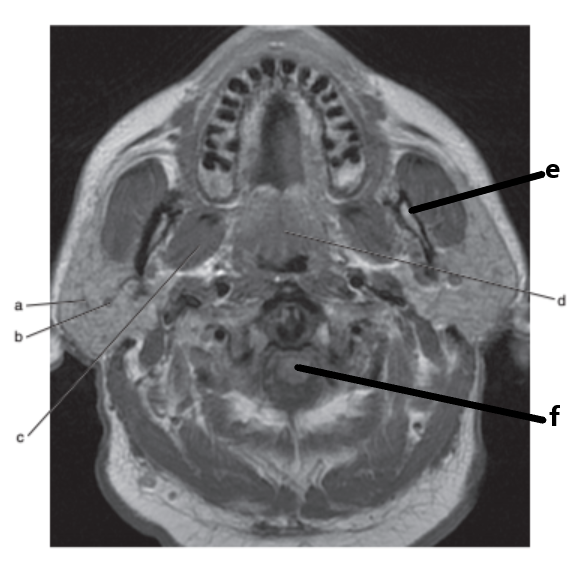

What imaging plane is this ?

transverse

What is letter a ?

Masseter muscle

Mandible

Parotid gland